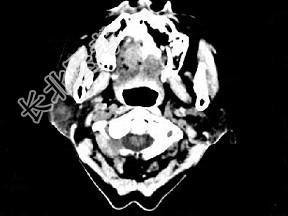

- 单项选择题女,72岁, 六年前于右面颊部扪及一包块,缓慢增大, 其表面较光滑,CT如图所示, 该病例应诊断为 ( )

A、Worthin瘤

B、腮腺混合瘤

C、颈部神经纤维瘤

D、颈部淋巴瘤

E、小唾液腺瘤